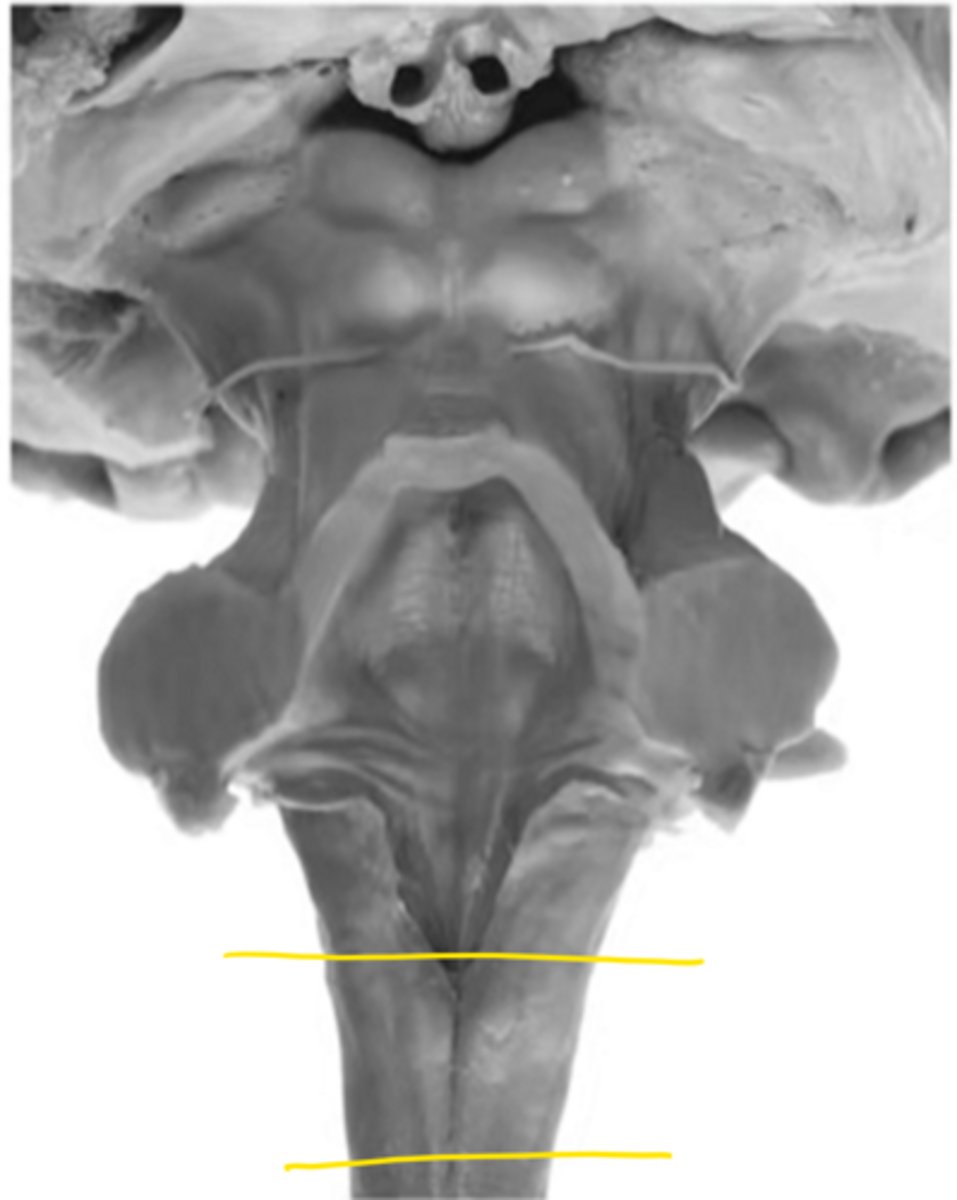

medulla

ID the area

medullary pyramids

ID the structure

anterior median sulcus

pyramidal decussation

olive

pre-olivary sulcus

open medulla

ID the brainstem level